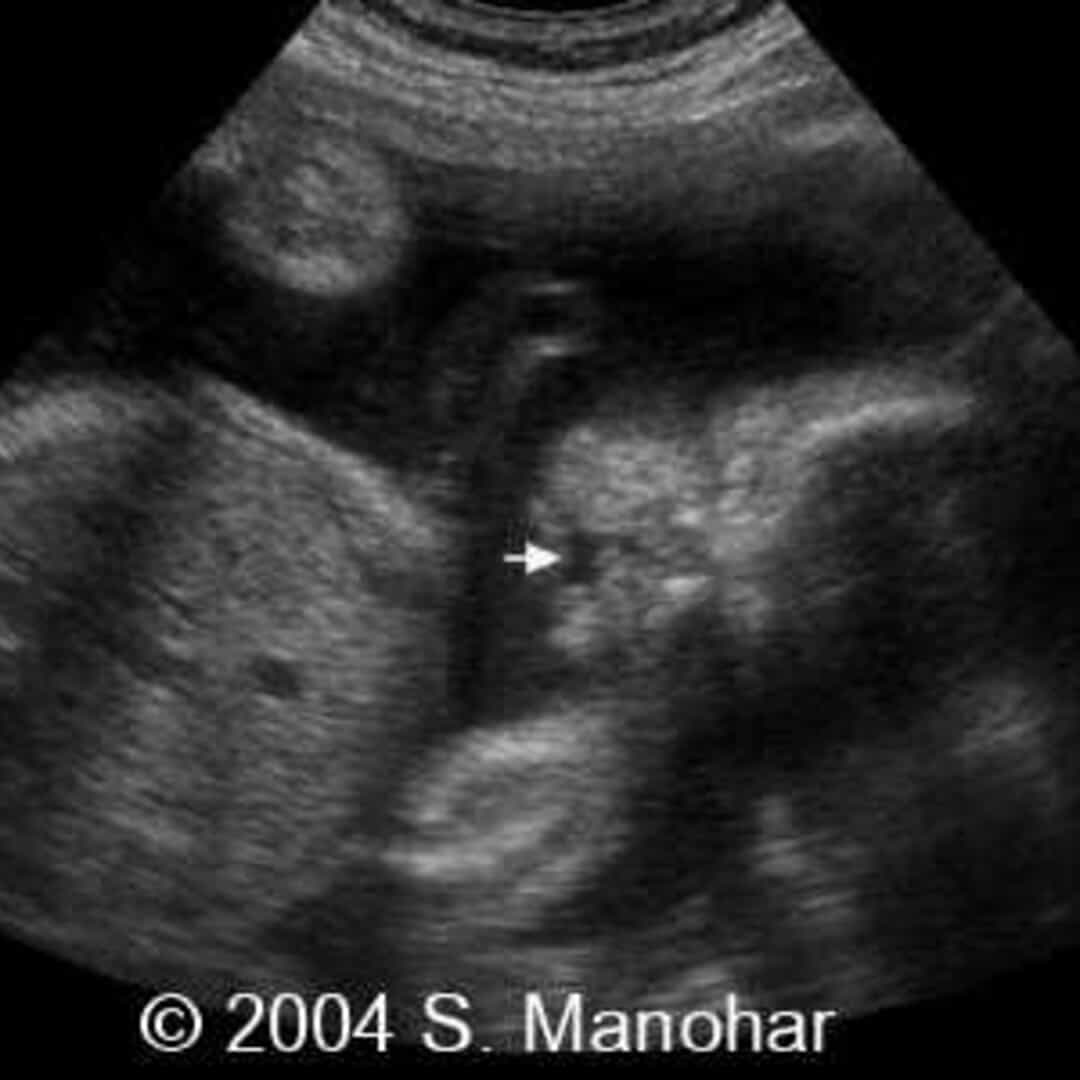

Ultrasound of Cleft. Cleft lip and palate blog Cleft lip, Cleft lip and palate, Cleft palate

Ultrasound of Cleft. Cleft lip and palate blog Cleft lip, Cleft lip and palate, Cleft palate What Does A Cleft Palate Look Like In An Ultrasound An ultrasound can often show a cleft lip alone or a cleft lip and palate at about 16 weeks into pregnancy. Only 7% of these appear on a prenatal ultrasound. Most cases of cleft lip and cleft palate are noticed right away at birth and don't require special tests for diagnosis. Isolated cleft palate (with no cleft lip present) is. What Does A Cleft Palate Look Like In An Ultrasound.